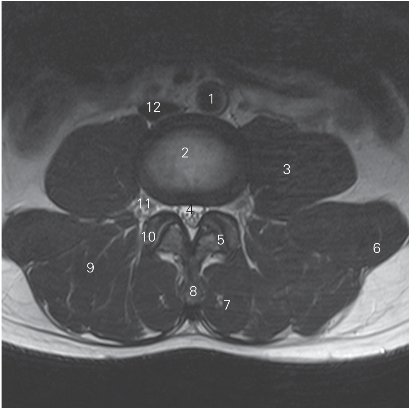

图3-9 经第4腰椎间盘的横断层MR T2加权图像

1 腹主动脉 abdominal aorta

2 第4腰椎间盘 4th lumbar intervertebral disc

3 腰大肌 psoas major 4 硬膜囊 dural sac

5 关节突关节 zygapophyseal joint 6 腰方肌 quadratus lumborum

7 多裂肌 multifidi 8 棘突 spinous process

9 竖脊肌 erector spinae

10 上关节突 superior articular process

11 腰神经 lumbar nerve 12 下腔静脉 inferior vena cava